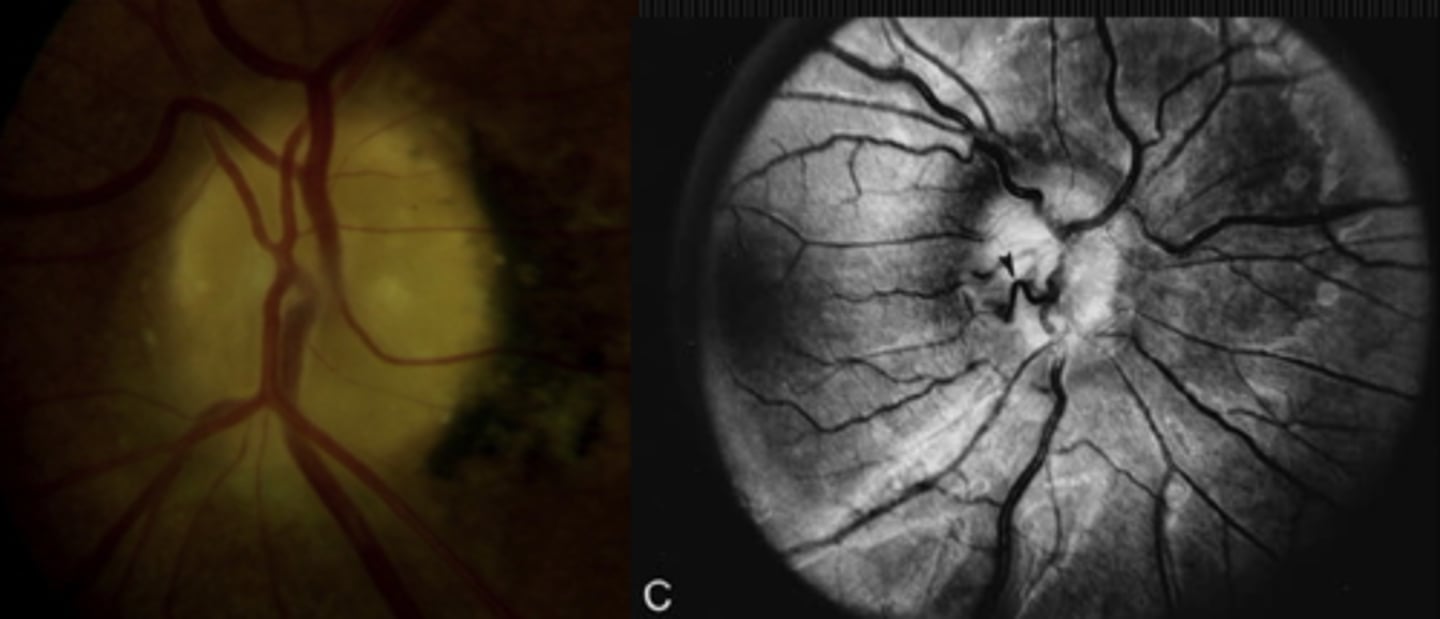

What cause of ascending optic atrophy is shown here?

RP

chronic atrophic papilledema